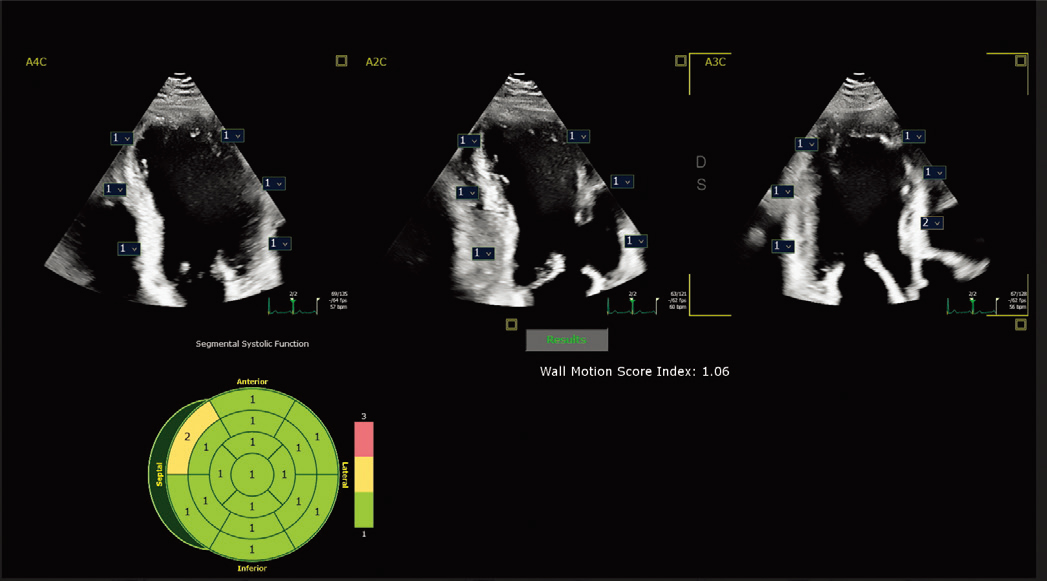

现配备 2D 自动 EF 和中间层应变 Advances 的进步之处在于,它能够在同一应用程序中提供快速、可重复的结果,作为全面 LV 评估的一部分,从而改善工作流程并节省时间。 | ![]() 自动节段性室壁运动评分* 在标准 17 段靶心显示屏上自动评估壁运动,以帮助客观评估 LV 壁。 |

X5-1c 探头进行自动节段性室壁运动评分指数 |